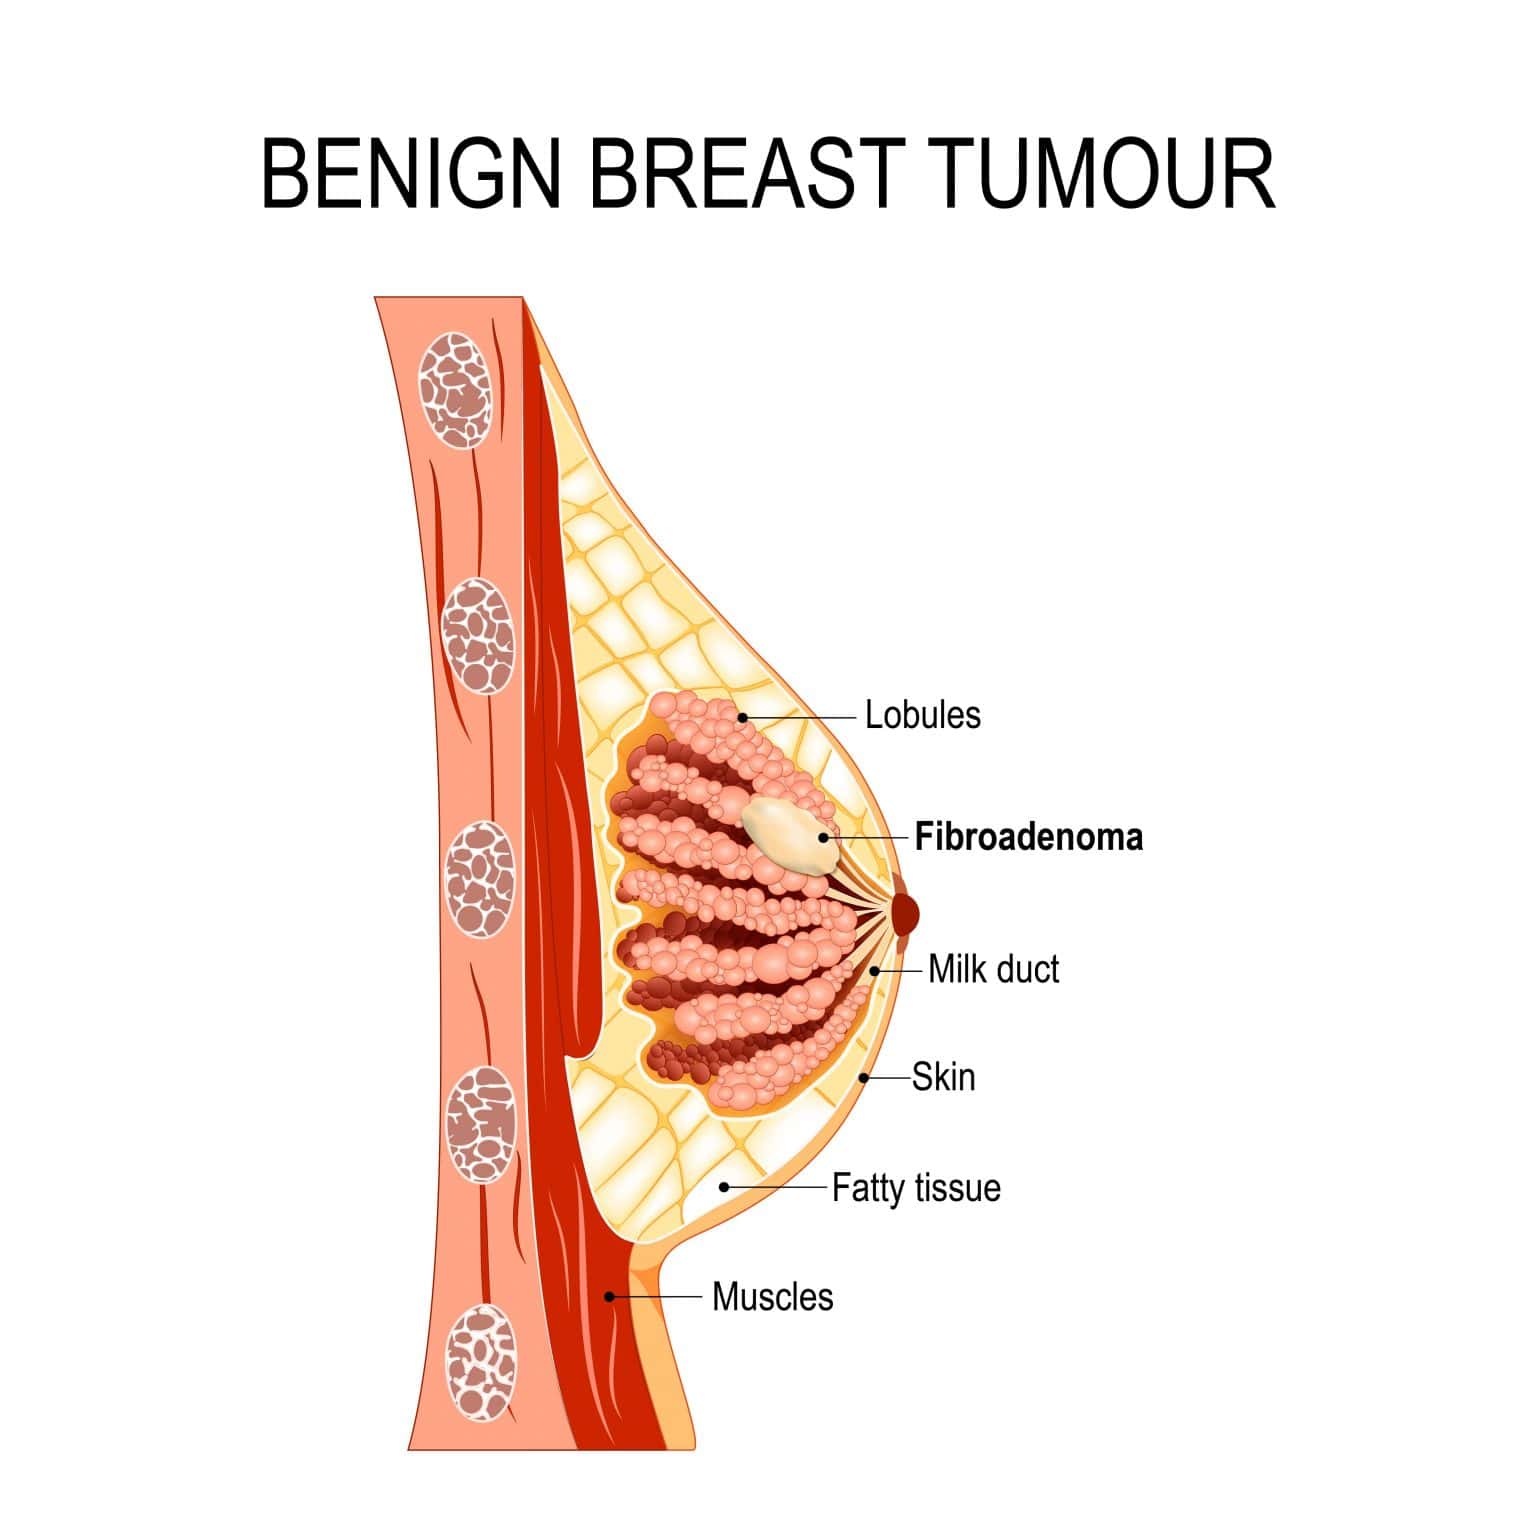

Уплотнения в груди могут быть вызваны различными причинами, включая кисты, фиброаденомы или инфекционные процессы. Важно понимать, как правильно подходить к их лечению и когда обращаться к врачу. Следующие советы помогут вам разобраться в этом вопросе и обеспечить здоровье своей груди.